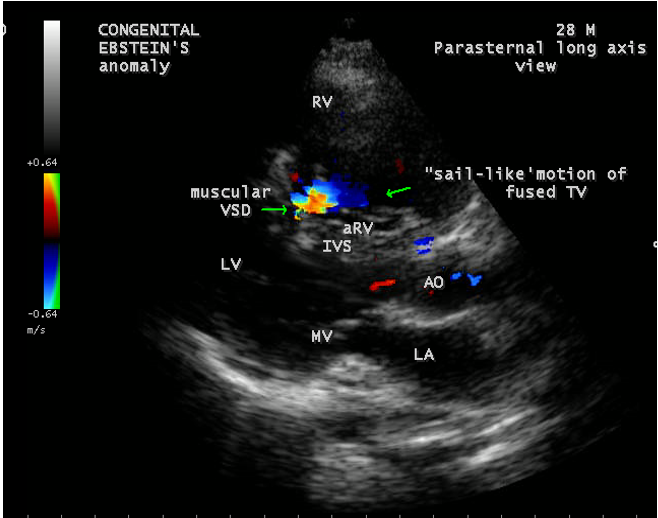

A 28-year old male presented with cyanosis and auscultation revealed a ‘sail sound’ ( loud tricuspid component of first heart sound due to increased tension developed by the large anterior leaflet as it reaches the limits of its systolic excursion- an important sign of anterior leaflet mobility), a ‘cadence’ quality of quadruple rhythm due to wide splitting of first and second sounds ( due to complete right bundle branch block), atrial and ventricular filling sounds (summation of these sounds due to prolonged PR interval). ECG revealed the features of Ebstein’s anomaly as shown in Figures 11 and 12. X-ray chest revealed the Ebstein’s configuration as shown in Figure 13. 2D echocardiography revealed a ‘sail-like’anterior tricuspid leaflet forming a ‘muscular curtain’ in between the inflow and trabecular parts of the right ventricle as an ‘imperforate membrane’ with a ‘pinhole’communication, associated with a muscular VSD (ventricular septal defect) in the proximal, atrialized compartment of right ventricle suggesting an ‘atretic” (‘imperforate’) Ebstein’s anomaly as shown in Figures 14 to 27.

The anterior tricuspid leaflet is not involved in the process of downward displacement, it may be abnormally inserted occasionally and Shiina, et al documented the apical displacement of anterior tricuspid leaflet in 14% of cases echocardiographically [39]. The anterior leaflet forms a large, sail-like intracavitary curtain as in Figures 14, 25 and contains muscular strands instead of consisting entirely of a fibrous membrane as in the normal tricuspid valve [40]. It is potentially mobile with a brisk sail-like movement as shown in Figure 21 to 24 [41], free bloating with a ‘whipping motion’ across the right ventricular outflow tract (RVOT) as shown in Figure 26 and in some cases, the movement is restricted due to its adherence to the ventricular wall as in Figure 1 and 2, 4 and 9. It is often fenestrated, may in part be musculaized , inserting into the trabeculations of the right ventricle (RV) as in Figure 28 and rarely, the anterior leaflet forms an ‘atretic’ membrane that spans the midportion of the right ventricular cavity as in Figure 16.

An interatrial communication is present in 80 to 94% of patients with Ebstein’s anomaly [50]. Ebstein believed that “regurgitation of blood into the right atrium caused its dilatation and prevented complete closure of the valve of foramen ovale”. The majority of hearts with Ebstein’s anomaly have a patent foramen ovale (67%) and in more than one third of cases, the interatrial communication is an ostium secundum defect as shown in Figures 1 and 2 . An intact atrial septum is rare and usually seen in adults as in Figure 4. The ventricular septal defect may be localized in either the proximal as shown in Figure 19 or the distal right ventricular compartment and it can be muscular with an incidence of 4% in clinical series and 12% in autopsy studies. The hearts in which the opening is proximal to the displaced tricuspid valve, a left ventricular to right atrial shunt may occur as shown in Figure 20

Ebstein’s original case was an example of obstruction at the tricuspid orifice by a membrane dividing the right ventricle into two halves as shown in Figure 16 of a 28-year old cyanotic male with ECG and X-ray characteristics as in Figure 11 to 13. suggesting an advanced spectrum of Ebstein’s malformation , necessitating RV exclusion techniques such as Starnes’ procedure. The florid case of Ebstein’s anomaly with the insertion of leaflet tissue along with ventricular walls as a ‘blanket’ as in Figures 28 and 29 in a 30-year old cyanotic male may go for an initial palliation with bidirectional Glenn shunt (cavopulmonary anastomosis). The other variants of moderate degree of leaflet tethering with varying degrees of regurgitation, but an intact basal leaflet attachments with atrioventricular junction as in Cases 1 and 2 may need a definite repair. In Ebstein’s mitral valve as in Figure 32 in a 10-year old boy, the downward displacement of functional annulus > 0.8 cm/m2 is not particularly striking and tends to affect the septal leaflet (anterior mitral leaflet) alone. The valve is thickened and mildly regurgitant due to rheumatic involvement rather than an anatomic cause.